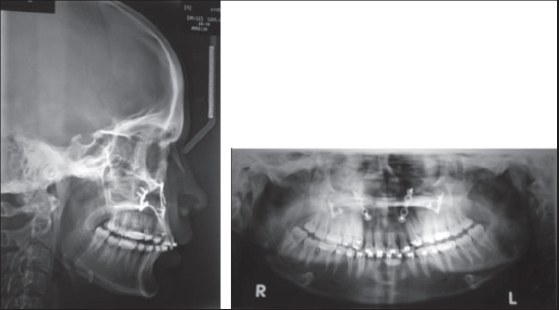

Figure 6: Preoperative lateral cephalogram and orthopantamogram-Group II

thumb

Figure 7: 1-week postoperative lateral cephalogram and orthopantamogram- Group II

Figure 8: 6-month postoperative lateral cephalogram and orthopantamogram- Group II